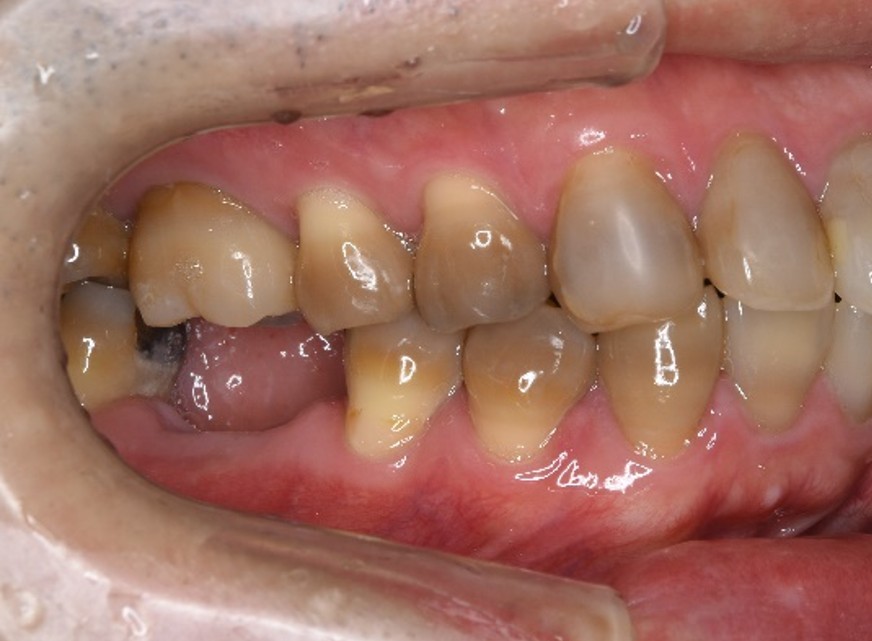

治療前